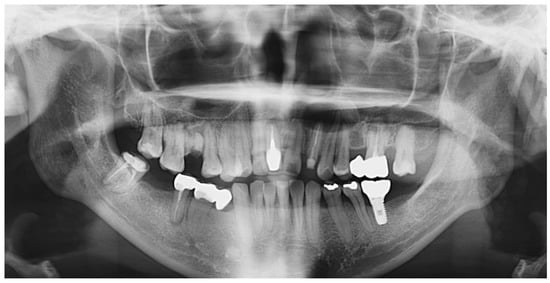

2. Case Presentation